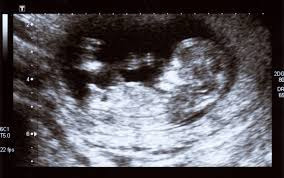

통증이 없고 방사선 노출도 없어 임산부, 노약자 모두에게 안전하게 사용할 수 있습니다.